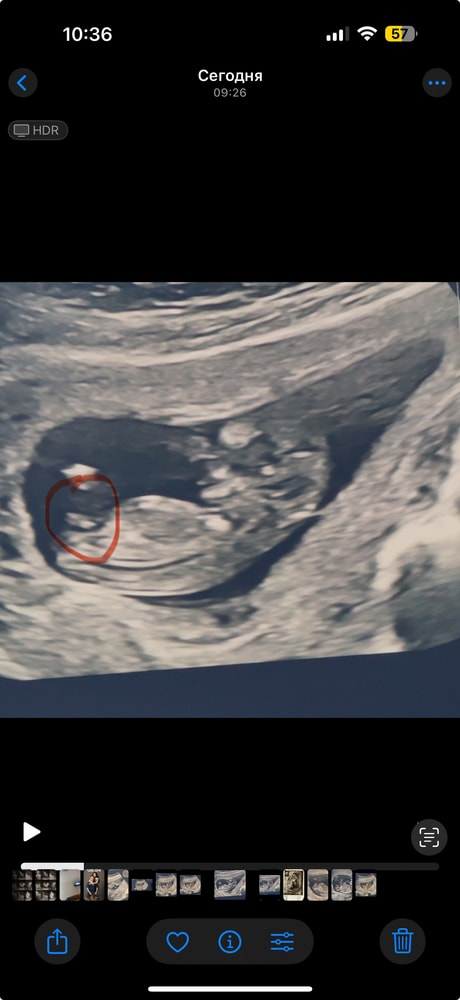

1 скрининг ,Мальчик наш🥹❤️

СкринингПервый скрининг пройден на отлично 🥹😍Моя 4 Ая беременность 😍🥹🥹🥹

сказали со здоровьем все хорошо,и Мальчик 80-90% 😍😍😍🥹🥹🥹🥹

После 3 девочек наш Принц идет 😭

вы тоже видите что Мальчуган?))

срок тут по узи 11,5 дней